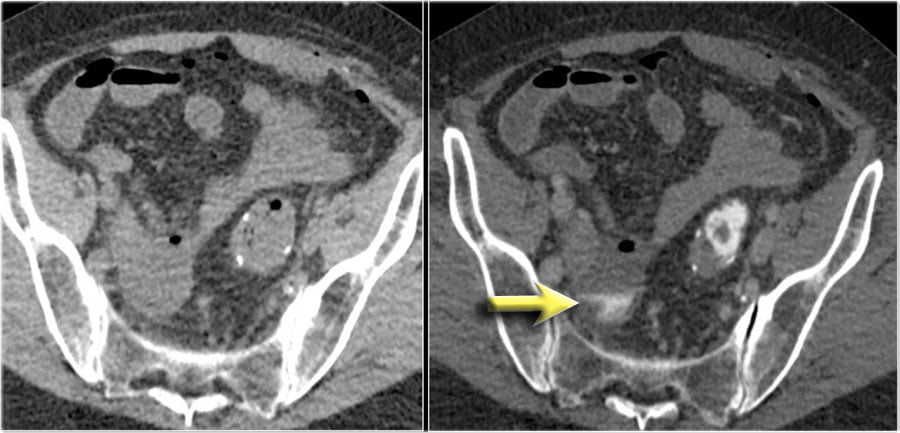

Here a patient with an anastomosis in the lower abdomen after resection of a sigmoid carcinoma.

Compare the NECT without oral or rectal contrast on the left with the images on the right after rectal contrast.

There is no doubt, that contrast in the fluid collection in the right lower abdomen is the result of leakage from the bowel (arrow).

Bệnh nhân bị rò mối nối sau mổ ung thư đại tràng sigma.

Hình bên trái không bơm thuốc so sánh với hình bên phải có bơm thuốc đường trực tràng.

Không còn nghi ngờ gì nữa, có thuốc cản quang trong vùng tụ dịch ở vùng bụng dưới bên phải là kết quả của sự rò từ ruột (mũi tên).